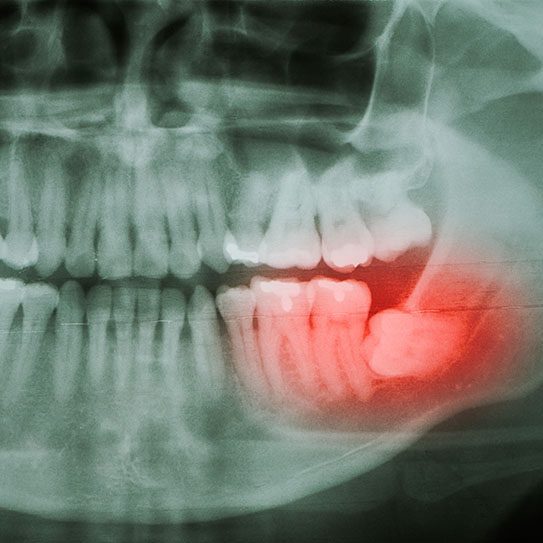

When Is Wisdom Tooth Removal Recommended?

Your Guide to Wisdom Teeth Extraction Wisdom tooth removal is a common dental procedure that many individuals undergo during their late teens or early adulthood. While not everyone needs to have their wisdom teeth removed, there are several situations where this treatment is recommended to prevent potential dental problems. If you’re wondering whether you or […]